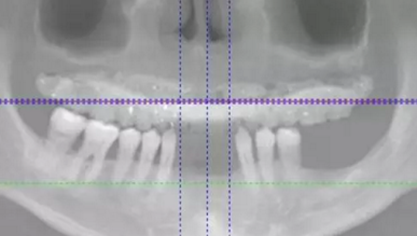

治療計(jì)劃及種植方案設(shè)計(jì)

患者骨高度嚴(yán)重不足,尤其是后牙區(qū),骨高度基本都只有2mm。按常規(guī)傾斜植入的方式也不可行,因此選擇在5號(hào)位通過(guò)內(nèi)提升方式植入植體。